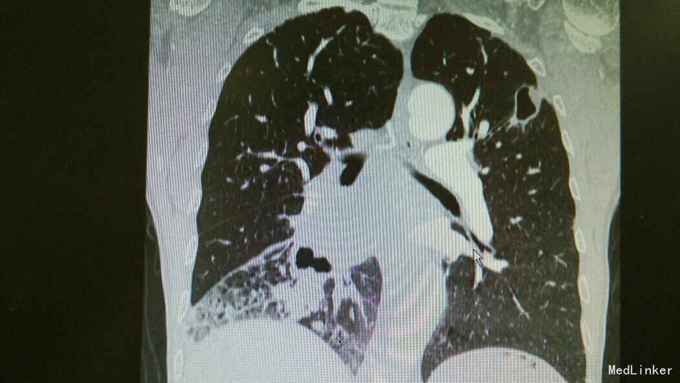

主诉:活动后气促,胸闷1年,消瘦8月余。 病史:患者1年前无明显诱因出现活动后气促,胸闷,主要为胸骨段,爬坡可诱发,伴有咳嗽,白色粘痰。伴有体重下降。

查体:慢性病容,桶状胸,双肺呼吸音粗,右下肺可闻及少量细湿罗音。 辅查:胸部CT:考虑右下肺中央型肺癌并癌性空洞形成,右下肺阻塞性肺炎 ,右下肺动静脉受累,纵隔,双侧肺门多发淋巴结肿大。

诊断:中央型肺癌并阻塞性肺炎。 治疗:入院予以抗感染,止咳化痰等治疗。